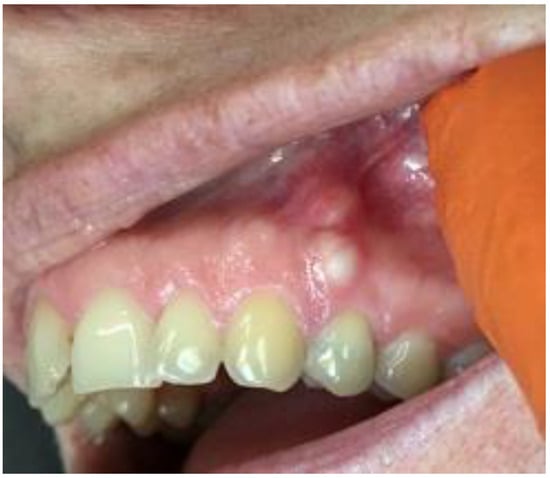

A 35-year-old female patient presented with a small, well-defined lesion on the attached gingival area, approximately 5/6 mm in diameter between roots of teeth 23–24, reported to the Privat Dental Clinic. The patient’s main concern was focused on gingival asymmetry and a tumor-like mass, painless and sometimes tender on tooth brushing. Clinical anamnesis revealed the occurrence of this asymptomatic mass for over 6 months. Because of swelling and atypical cortical expansion, the patient was referred for consultation and treatment. The patient was generally healthy without any chronic illness or important medical and dental past. A routine panoramic radiograph revealed a well-defined, radiolucent, left maxillary lesion located between the roots of the canine and first maxillary premolar (Figure 1 and Figure 2).

Figure 2. LPC expanding towards attached gingiva with buccal cortical plate resorption.